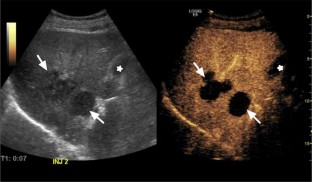

Liver lesions are often incidentally detected on ultrasound examination and may be incompletely characterized, requiring further imaging. Contrast-enhanced ultrasound (CEUS) was recently approved by the Food and Drug Administration in the United States for liver lesion characterization. CEUS has the ability to characterize focal liver lesions and has been shown to be superior to color Doppler and power Doppler ultrasound in the detection of tumor vascularity. Differentiating benign from malignant liver lesions is essential to characterizing liver lesions. The CEUS imaging characteristics of benign liver lesions are reviewed, including hepatic cysts, hemangiomas, focal fat, focal nodular hyperplasia, hepatocellular adenomas, abscesses, and traumatic lesions.

Fig. 1

Fig. 2

Fig. 3

Fig. 4

Fig. 5

Fig. 6

Fig. 7

Fig. 8

Fig. 9

Fig. 10